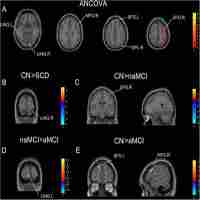

| Abstract | Objective:This study investigated white matter integrity in patients with amnestic mild cognitive impairment by diffusion tensor imaging.Methods:A total of 83 patients with amnestic mild cognitive impairment and 85 elderly healthy controls underwent neuropsychological testing and a diffusion tensor imaging scan. Whole-brain white matter data were parcellated into 50 regions based on the anatomical ICBM-DTI-81 atlas, and regional diffusion metrics consisting of fractional anisotropy, mean diffusivity, radial diffusivity, and axial diffusivity were calculated for each region. Diffusion tensor imaging indices were compared between groups, and it was determined that between-group differences were significantly correlated with neurocognitive performance.Results:Relative to the healthy controls group, the amnestic mild cognitive impairment group exhibited poorer cognitive performance in all neuropsychological tests except the complex figure test (p = 0.083) and showed decreased mean fractional anisotropy in the fornix, increased mean diffusivity in the fornix and bilateral uncinate fasciculus, elevated axial diffusivity in the fornix and genu of corpus callosum, and elevated radial diffusivity in the fornix and bilateral uncinate fasciculus (p < 0.05). Behaviorally, integrity of the bilateral uncinate fasciculus was correlated positively with episodic memory function, while left uncinate fasciculus integrity was positively associated with language function in the amnestic mild cognitive impairment group (p < 0.05).Conclusion:White matter abnormalities in neural pathways associated with memory were correlated with neurocognitive deficiencies in amnestic mild cognitive impairment. Given that amnestic mild cognitive impairment is putatively a prodromal syndrome for Alzheimer’s disease, this study furthers our understanding of the white matter changes associated with Alzheimer’s disease pathogenesis in the predementia stage. |